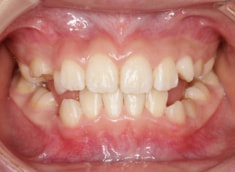

治療前